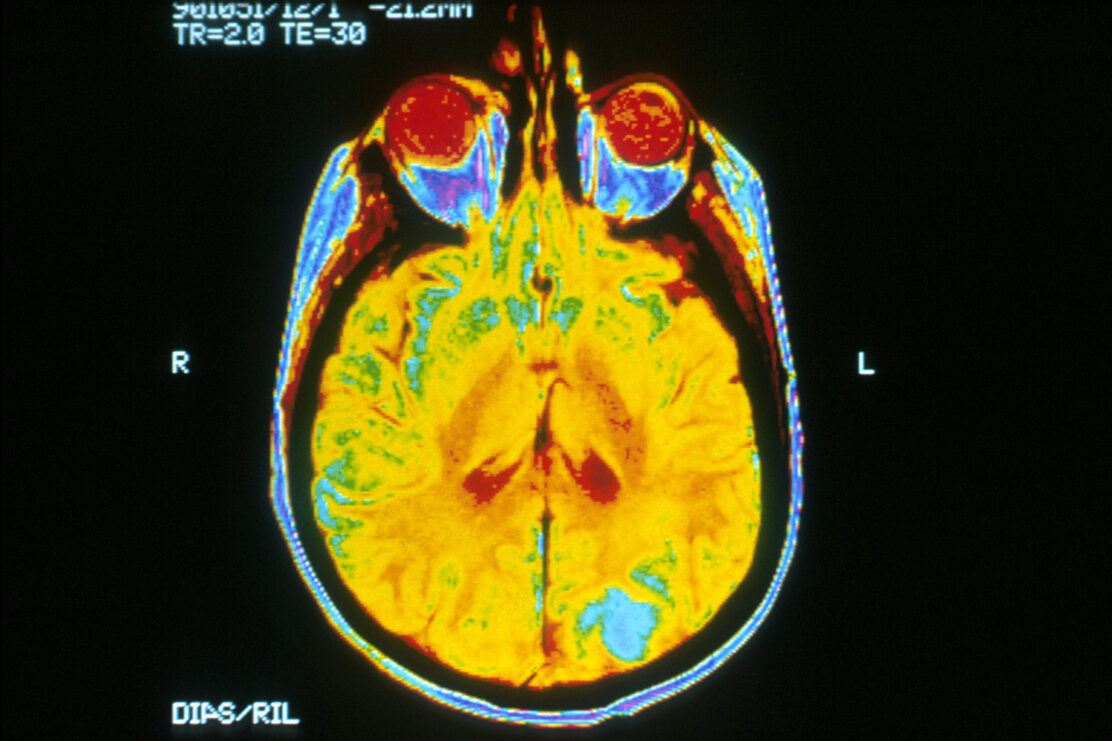

Obraz MRI ludzkiego mózgu z widocznym ogniskiem przerzutowym nowotworu w płacie potylicznym (zaznaczonym jasnoniebieskim kolorem).

Źródło: Dr Leon Kaufman, University of California, San Francisco / domena publiczna